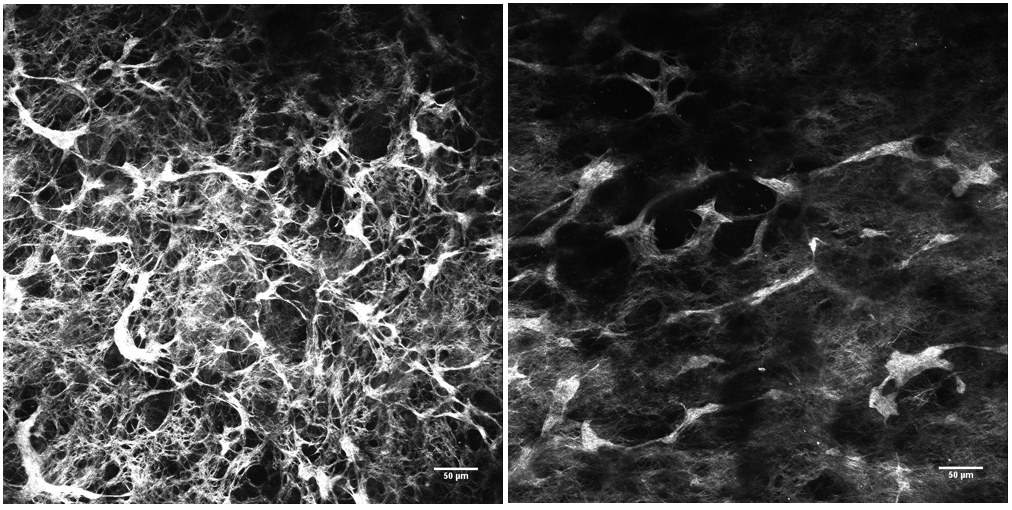

Au cours de la phase initiale d’essais en laboratoire, l’équipe de chercheurs a eu recours à l’impression 3D pour créer des modèles de peau et étudier l’efficacité de ce complexe. Cette méthodologie innovante, la bio-impression assistée par laser, consiste à générer un modèle de peau humaine à partir de cellules cutanées. Elle permet de réaliser des essais rapides et réalistes avant de passer à la phase in vivo. À ce stade, le nouveau complexe a permis de générer un réseau de collagène bien plus dense que le mélange contrôle, une association de peptides standard disponible sur le marché. La visualisation par génération de seconde harmonique (SHG), un processus optique de haute précision doté de la technologie laser, a démontré l’amélioration de la densité. En un mot, les photons émis par les rayons laser se comportent différemment selon les matériaux avec lesquels ils interagissent. Ces différences sont visualisées sous forme d’image : dans ce cas précis, celle des fibres de collagène dans les échantillons de peau imprimée en 3D (cf. Figure 1).